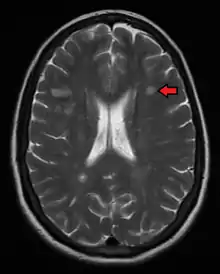

Magnetic resonance imaging (MRI) of the brain and spine may show areas of demyelination (lesions or plaques). Gadolinium can be administered intravenously as a contrast agent to highlight active plaques, and by elimination, demonstrate the existence of historical lesions not associated with symptoms at the moment of the evaluation.[69][70]